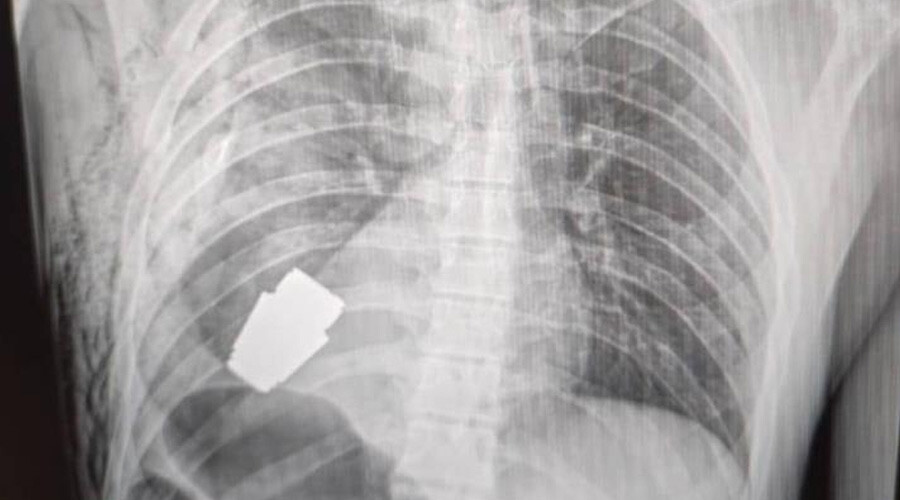

Ukrayna’da bir askerin vücudundan el bombası çıktı. Kalbine yakın bir bölgede bulunan bombanın patlamamış olduğu tespit edildi. Doktorlar bombanın patlama ihtimaline karşı hızlı bir operasyonla 275 gram ağırlığındaki el bombasını askeri vücudundan çıkardı.

Ukrayna'da bir askerin kalbine yakın bir bölgede patlamamış bir el bombası tespit edildi. El bombasının askerin vücuduna nasıl girdiğine dair bilgi verilmedi. Ukrayna Silahlı Kuvvetleri'nin en deneyimli cerrahlarından biri olarak kabul edilen 57 yaşındaki askeri doktor, el bombası 'her an patlayabileceği' için hızlı bir operasyon gerçekleştirdi.

Ameliyatın başarılı geçtiğini bildiren savunma bakanı yardımcısı askerin tedavi altına alındığını aktardı. Savunma Bakan Yardımcısı Hanna Malyar yapılan operasyona ilişkin şu ifadeleri kullandı, "Bu bir şok. Şükür ki, kalpteki yaralanma ölümcül değil." Ameliyat sonrası incelenen bombanın 40 mm'lik namlulu el bombası, olduğu ağırlığının ise yaklaşık 275 gram olduğu bilgisi verildi.